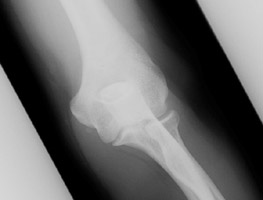

Similar to Pelligrini-Stieda disease of the knee, repetitive injury to the elbow may result in calcification of portions of the ulnar collateral ligament. These patients are at risk for rupture of this ligament.

- Click on the image for a larger versionAAP radiograph of the elbow. This shows heterotopic calcification at the ulnar side of the elbow, due to calcification of the ulnar collateral ligament.